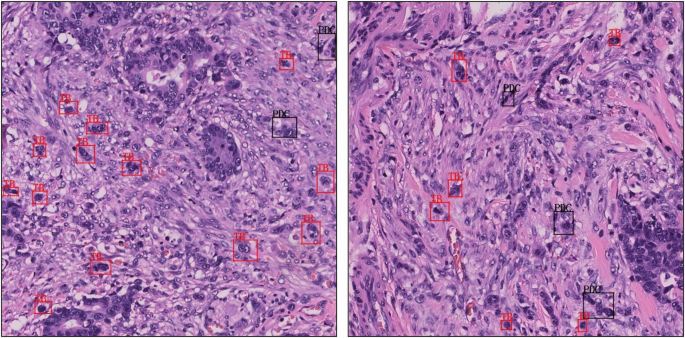

Development of the TBAM-TIFP

The development of the TBAM-TIFP mainly consisted of three phases: manually annotating TB hotspots and extracting patches, annotating TBs and poorly differentiated clusters (PDCs) in the patches, and training a TB annotation model in the patches.

Next, pathologists used professional software Labeling to annotate TBs and poorly differentiated cell clusters (PDCs) in each extracted patches, focusing on their location, morphology, and size. The annotations were carefully cross-checked to form a structured, high-quality annotated dataset of patches, providing a solid foundation for model training. For each patche \({P}_{i}\), the annotated TBs and PDCs were represented as:

where \(j=\mathrm{1,2},\ldots ,{m}_{i}\) \({t}_{j}\) was the specific type of the annotations, \(({x}_{j},{y}_{j})\) were the coordinates of the bounding box center, and \({w}_{j}\) and \({h}_{j}\) were the width and the height of the bounding box, respectively. The examples of the annotation in patches were shown in Fig. 13.

Examples of TB and PDC annotations in tumor invasive front patches by Labelimg.